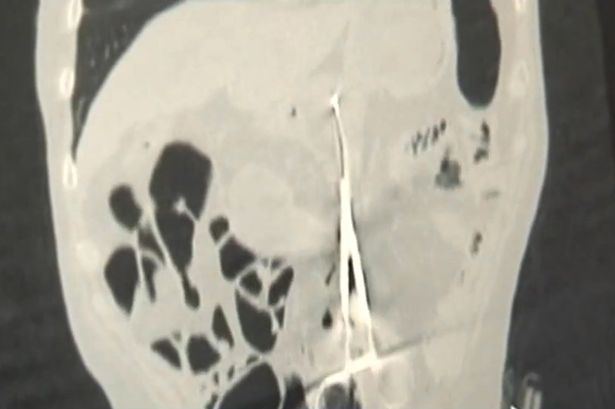

Ảnh chụp X-quang cho thấy chiếc kéo 20cm trong dạ dày bệnh nhân

Bác sĩ Baurzhan Aybaev (44 tuổi) – người kiểm tra kết quả chụp X-quang cho Karp Ponomaryov – cho biết: “Tôi chưa bao giờ thấy bất cứ chuyện gì như thế này. Tôi đã từng thấy miếng gạc phẫu thuật hoặc các thiết bị nhỏ bị bỏ lại nhưng chúng được phát hiện sớm hơn. Có lẽ bệnh nhân đã chịu đau đớn rất nhiều”.